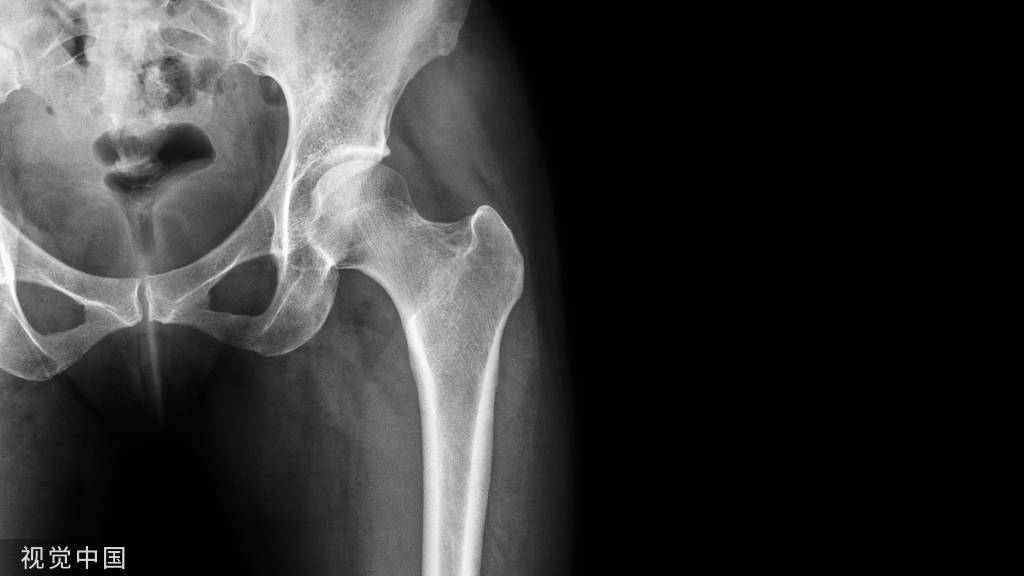

骨盆背面观显示臀上神经在髂后上棘外侧8cm处跨过髂嵴后方。